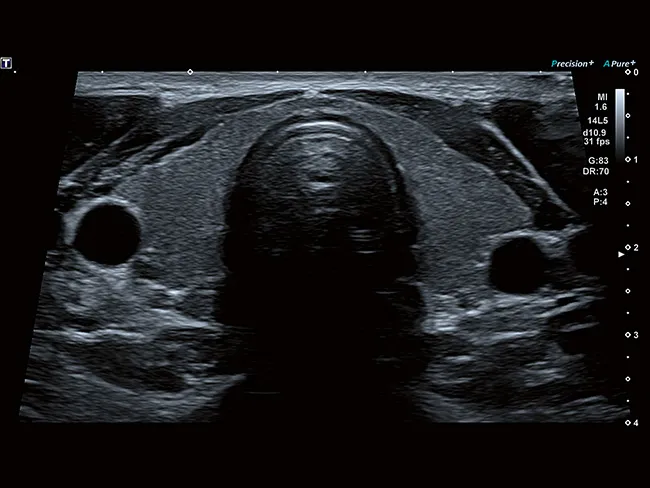

Исключительная детализация для более точной диагностики

Как занятый врач, так и пациент могут воспользоваться 2D-визуализацией высокого разрешения и объемным ультразвуковым исследованием. Комплексный пакет объемной визуализации Aplio расширяет ваши диагностические возможности и выходит на новый уровень визуализации благодаря исключительному качеству изображения и бескомпромиссному рабочему процессу.

Широкий спектр опций MultiView позволяет получать поперечные срезы с высоким разрешением, помогая лучше понять анатомические взаимосвязи или степень данного поражения.